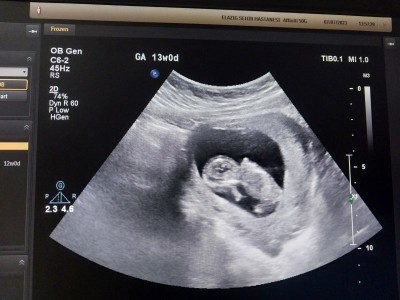

Bebeğimin sekli korkuttu sizce bir sorun var mı?

Hareket ettiği için o an baktığımızda öyle görmüşüz dimi benim ilk gebeliğim pek bilgim de yok korkuyorum açıkçası bisey olacak diye